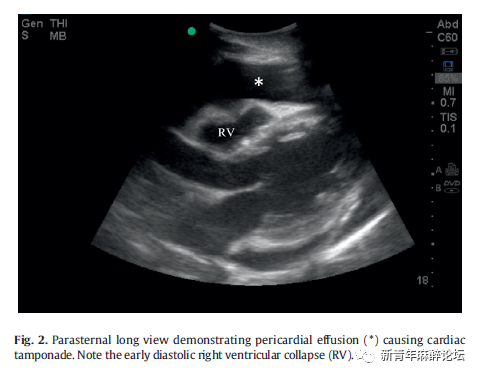

2.1. 第一步:心包填塞

心脏骤停患者中4-15%的原因是心包积液[5,13-16]。快速解除填塞后PEA通常可以得到解决 ,并且心包填塞患者至出院时的存活率(15.4%)比引起PEA的其他原因(1.3%)高[5]。检查者应评估心包积液,如果存在心包积液的迹象,应评估如舒张早期右室塌陷情况(Fig.2).如果存在心包填塞,则立即考虑行心包穿刺术。